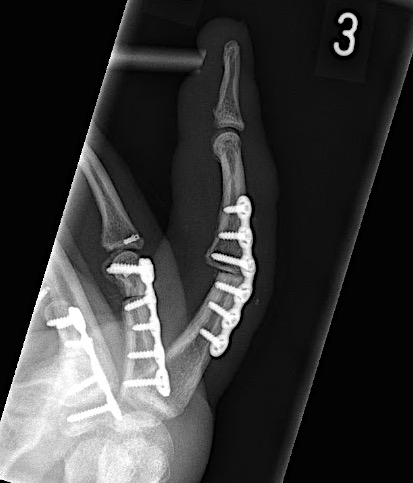

A 64-year-old male suffered a multi-fragmentary fracture of his right thumb metacarpal (Fig 1). An adapted 12-hole strut plate from the variable angle locking hand system was the implant of choice for fixation (Figs 2 - 4).

The strut plate provided good stability in a comminuted extraaricular fracture pattern and enables immediate mobilization. Bone callus formation was not witnessed during the healing process.